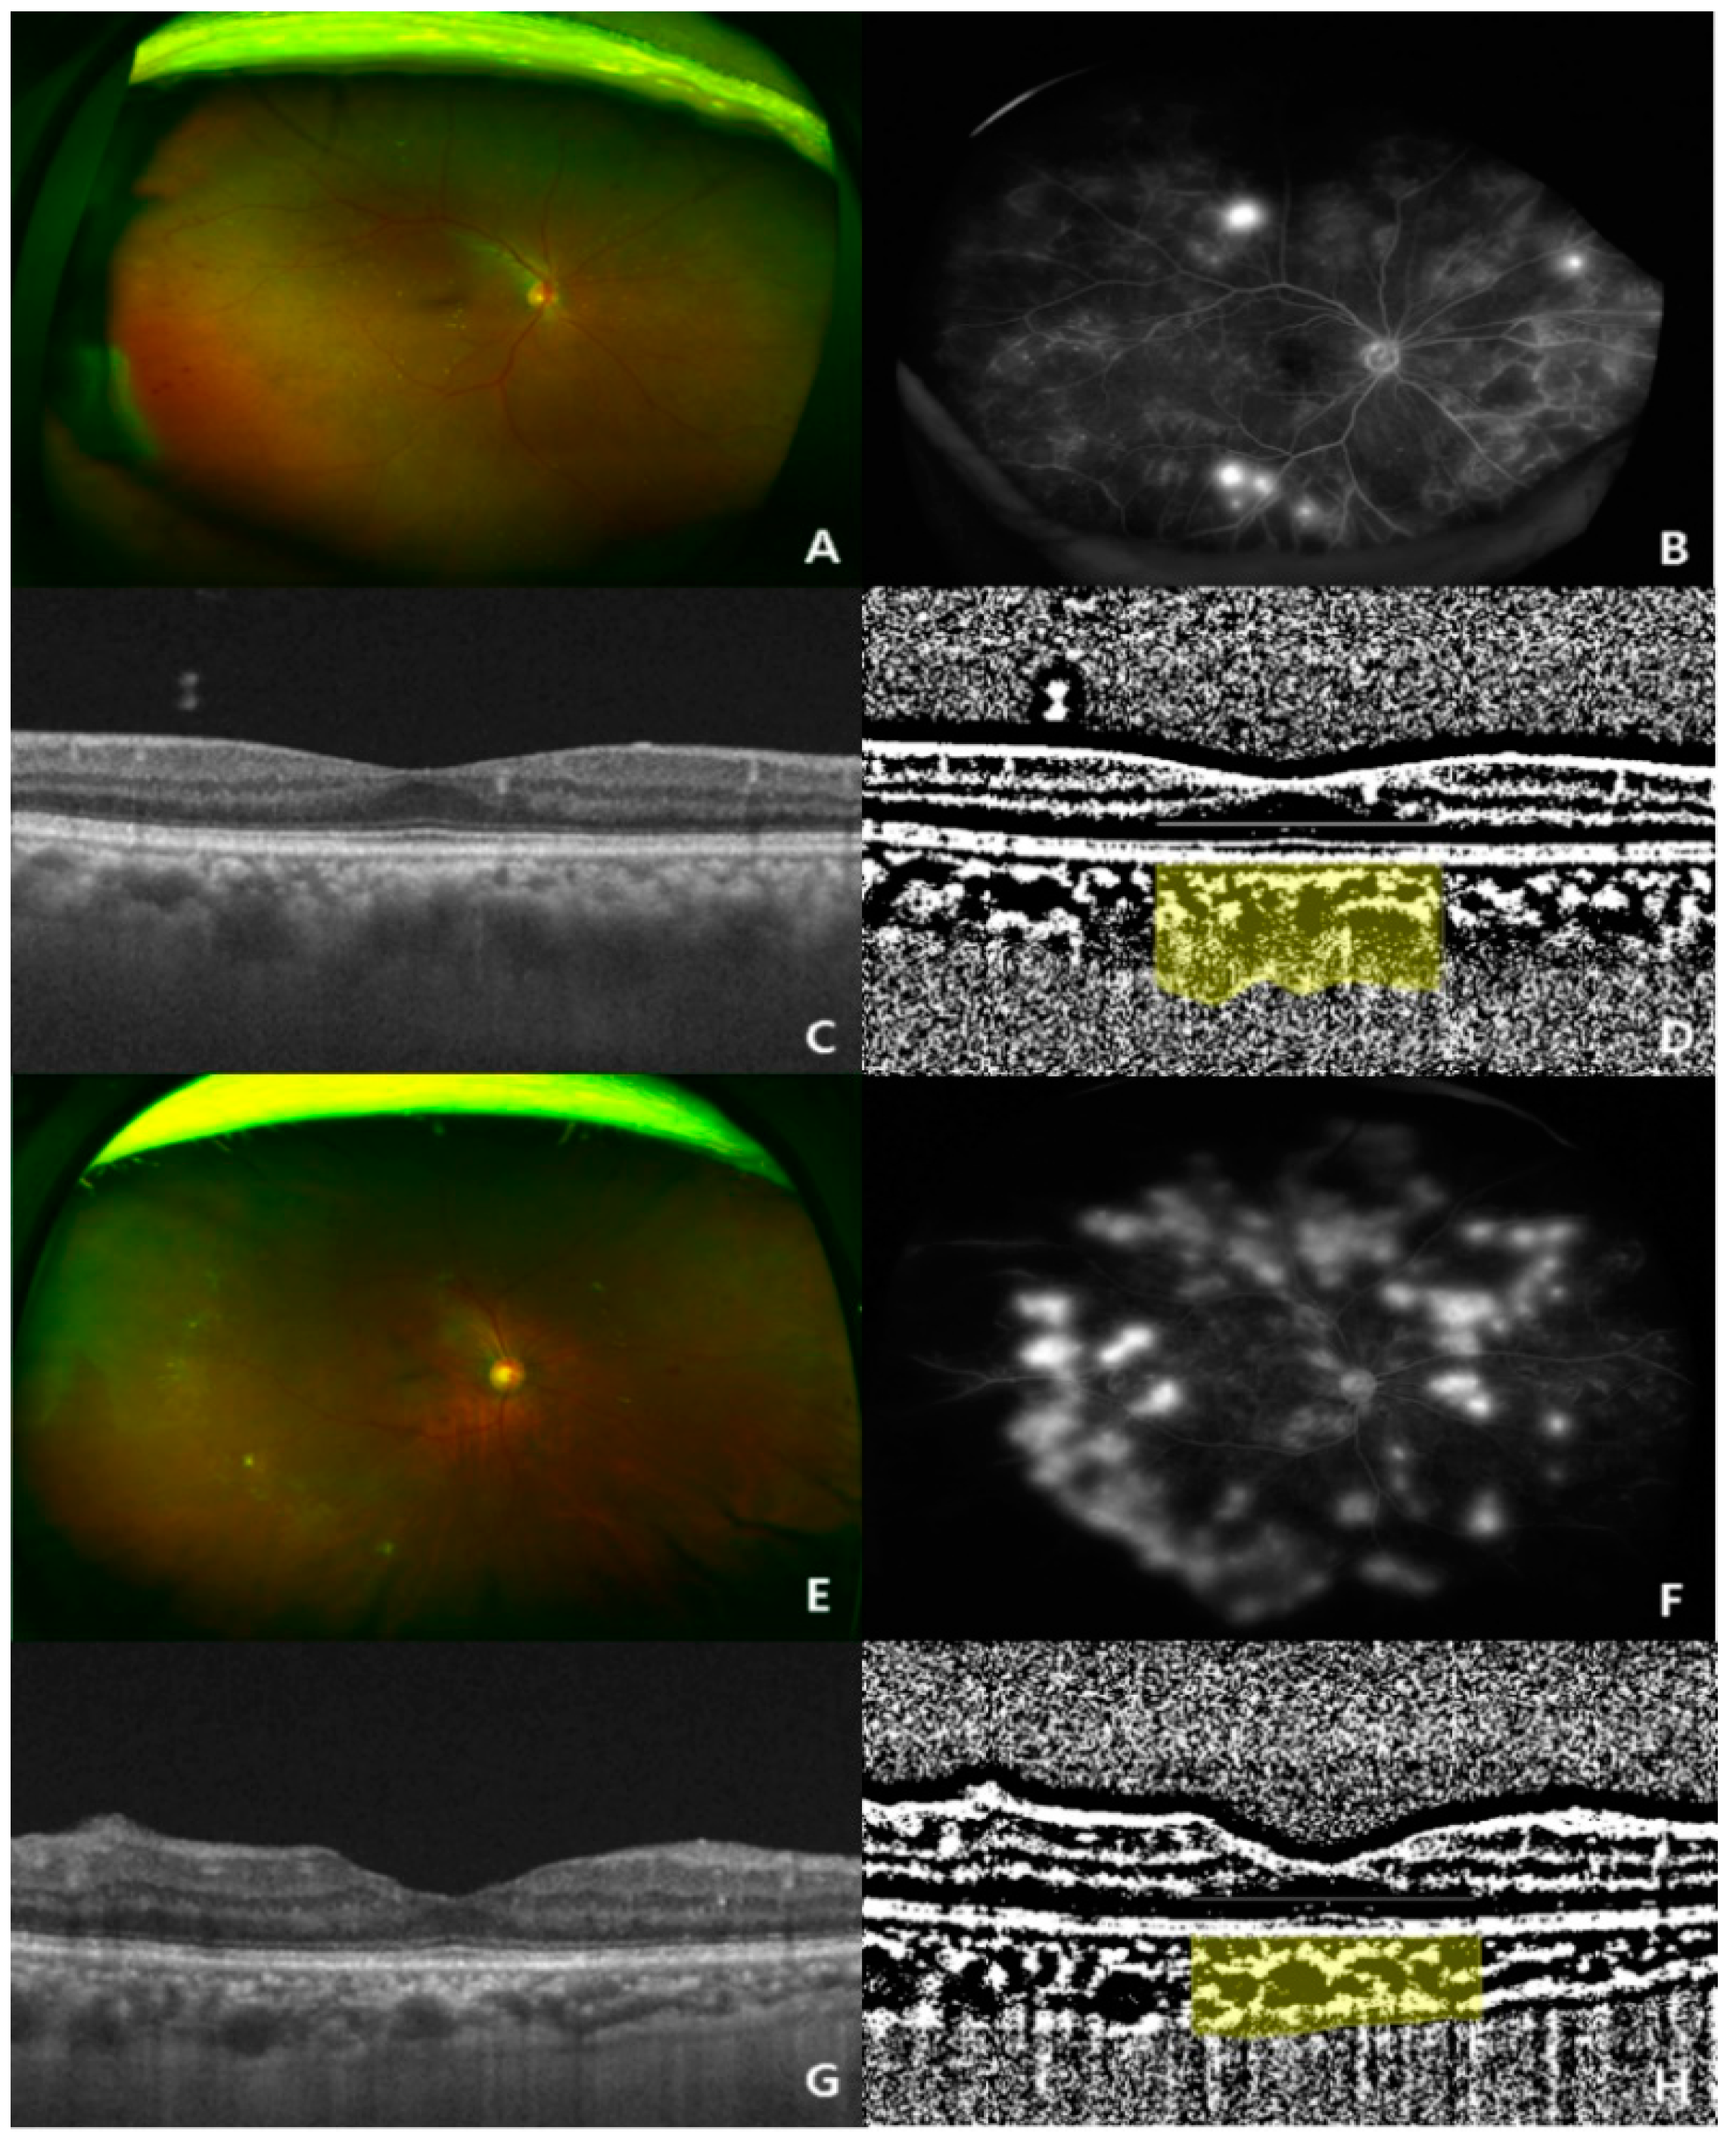

2.4. OCT

2.5. CVI